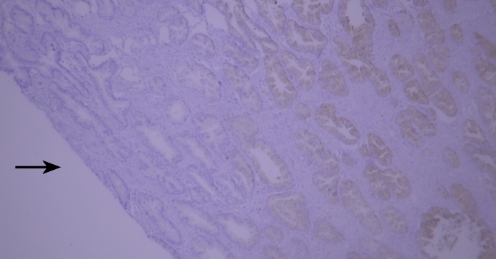

Typical example: CEA staining of paraffin-embedded human colon cancer tissue sections showed accumulation of staining solution (indicated by black arrows).

Recommendation for Resolution: Sufficient washing should be ensured during the experiment to avoid abnormal results caused by residual staining solution.